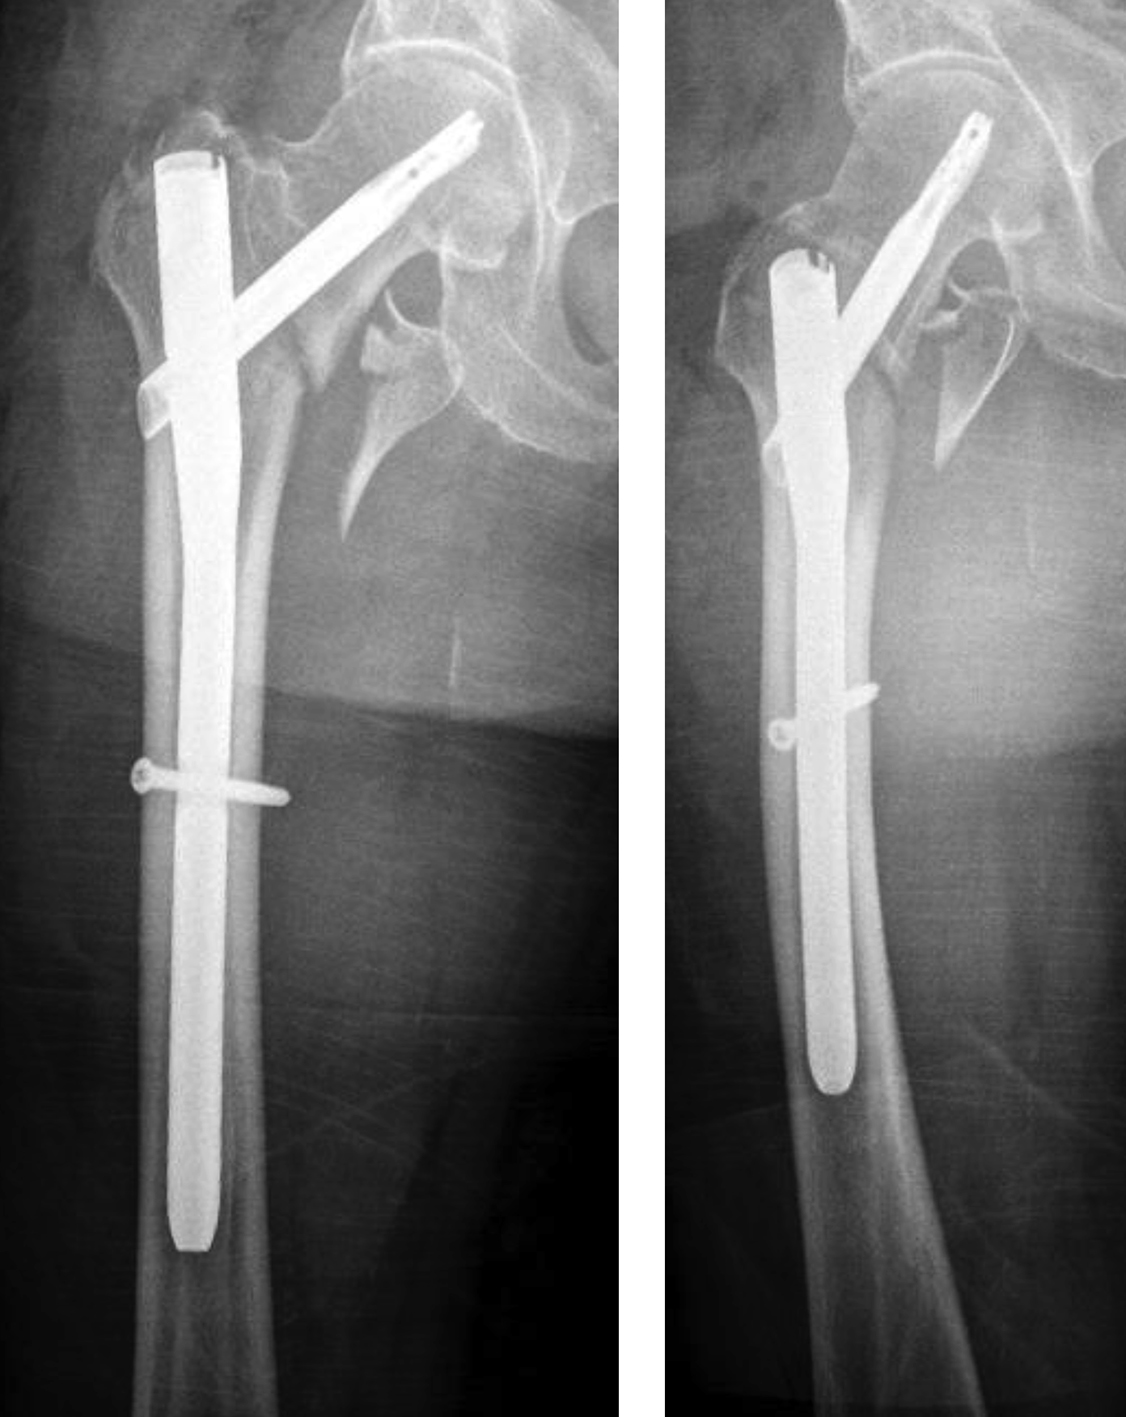

An 83-year-old female patient sustained a 31-A.2.2 fracture of the right proximal femur after a fall at home (Figs 1-2). Intraoperative and postoperative images are shown (Figs 3-5).